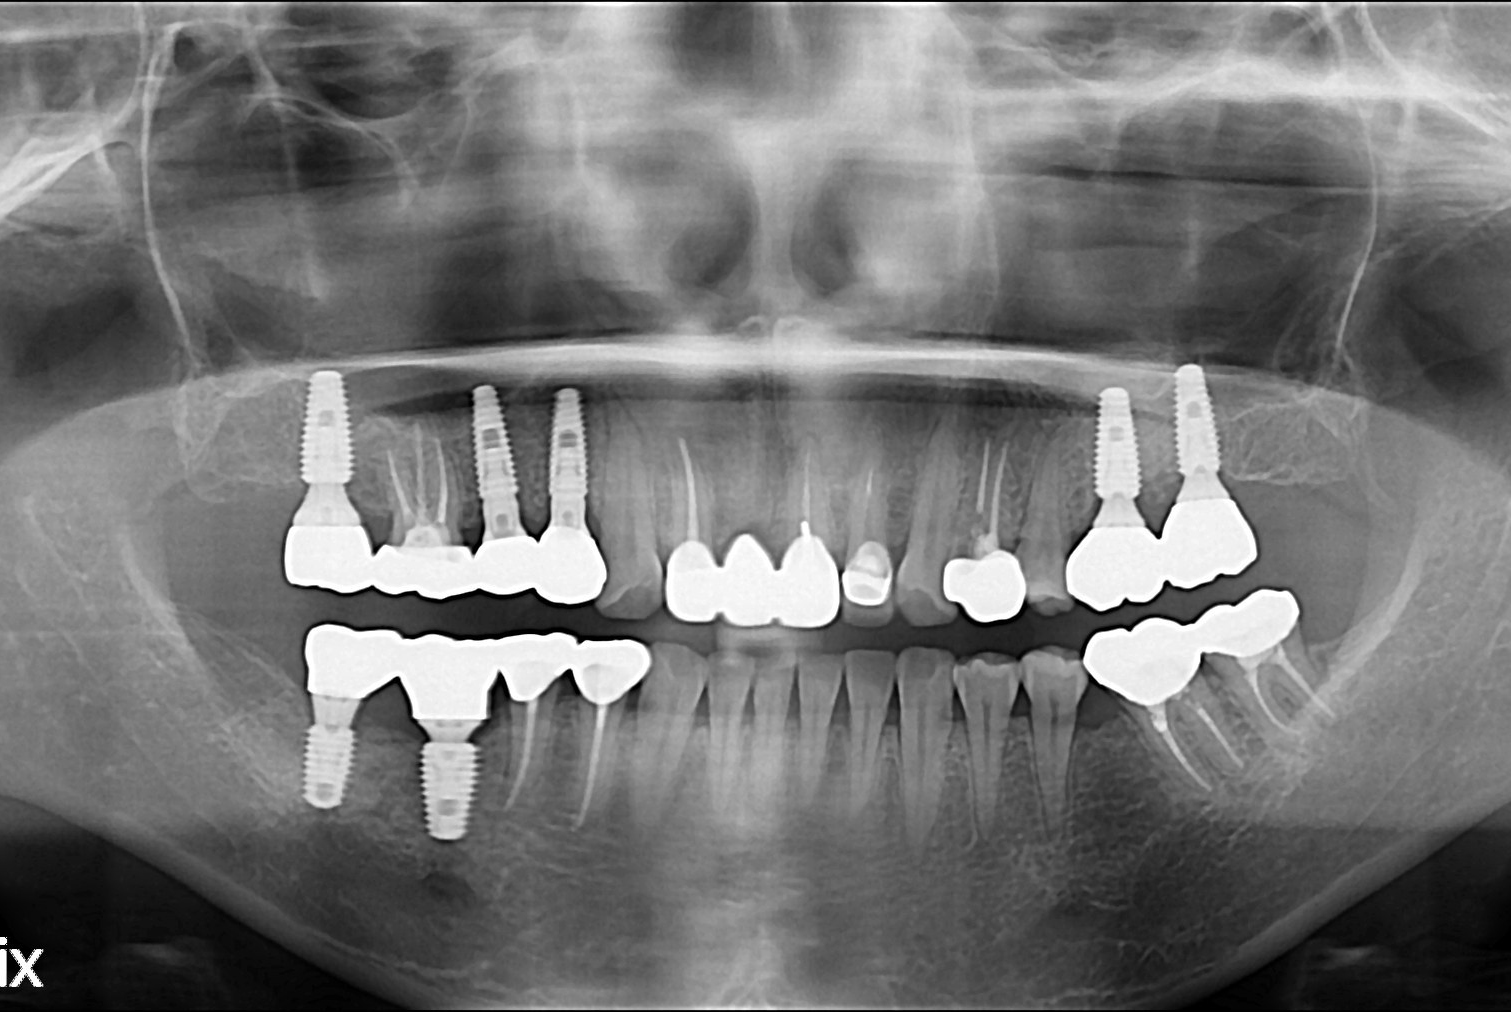

치료후 : 2019-05-17

세종치과는 많은 환자와 다양한 케이스를 바탕으로 항상 편안한 임플란트 수술을 제공하고자 노력하고,

오래동안 튼튼히 쓸 수 있는 임플란트 수술을 가장 큰 목표로 삼고 있습니다